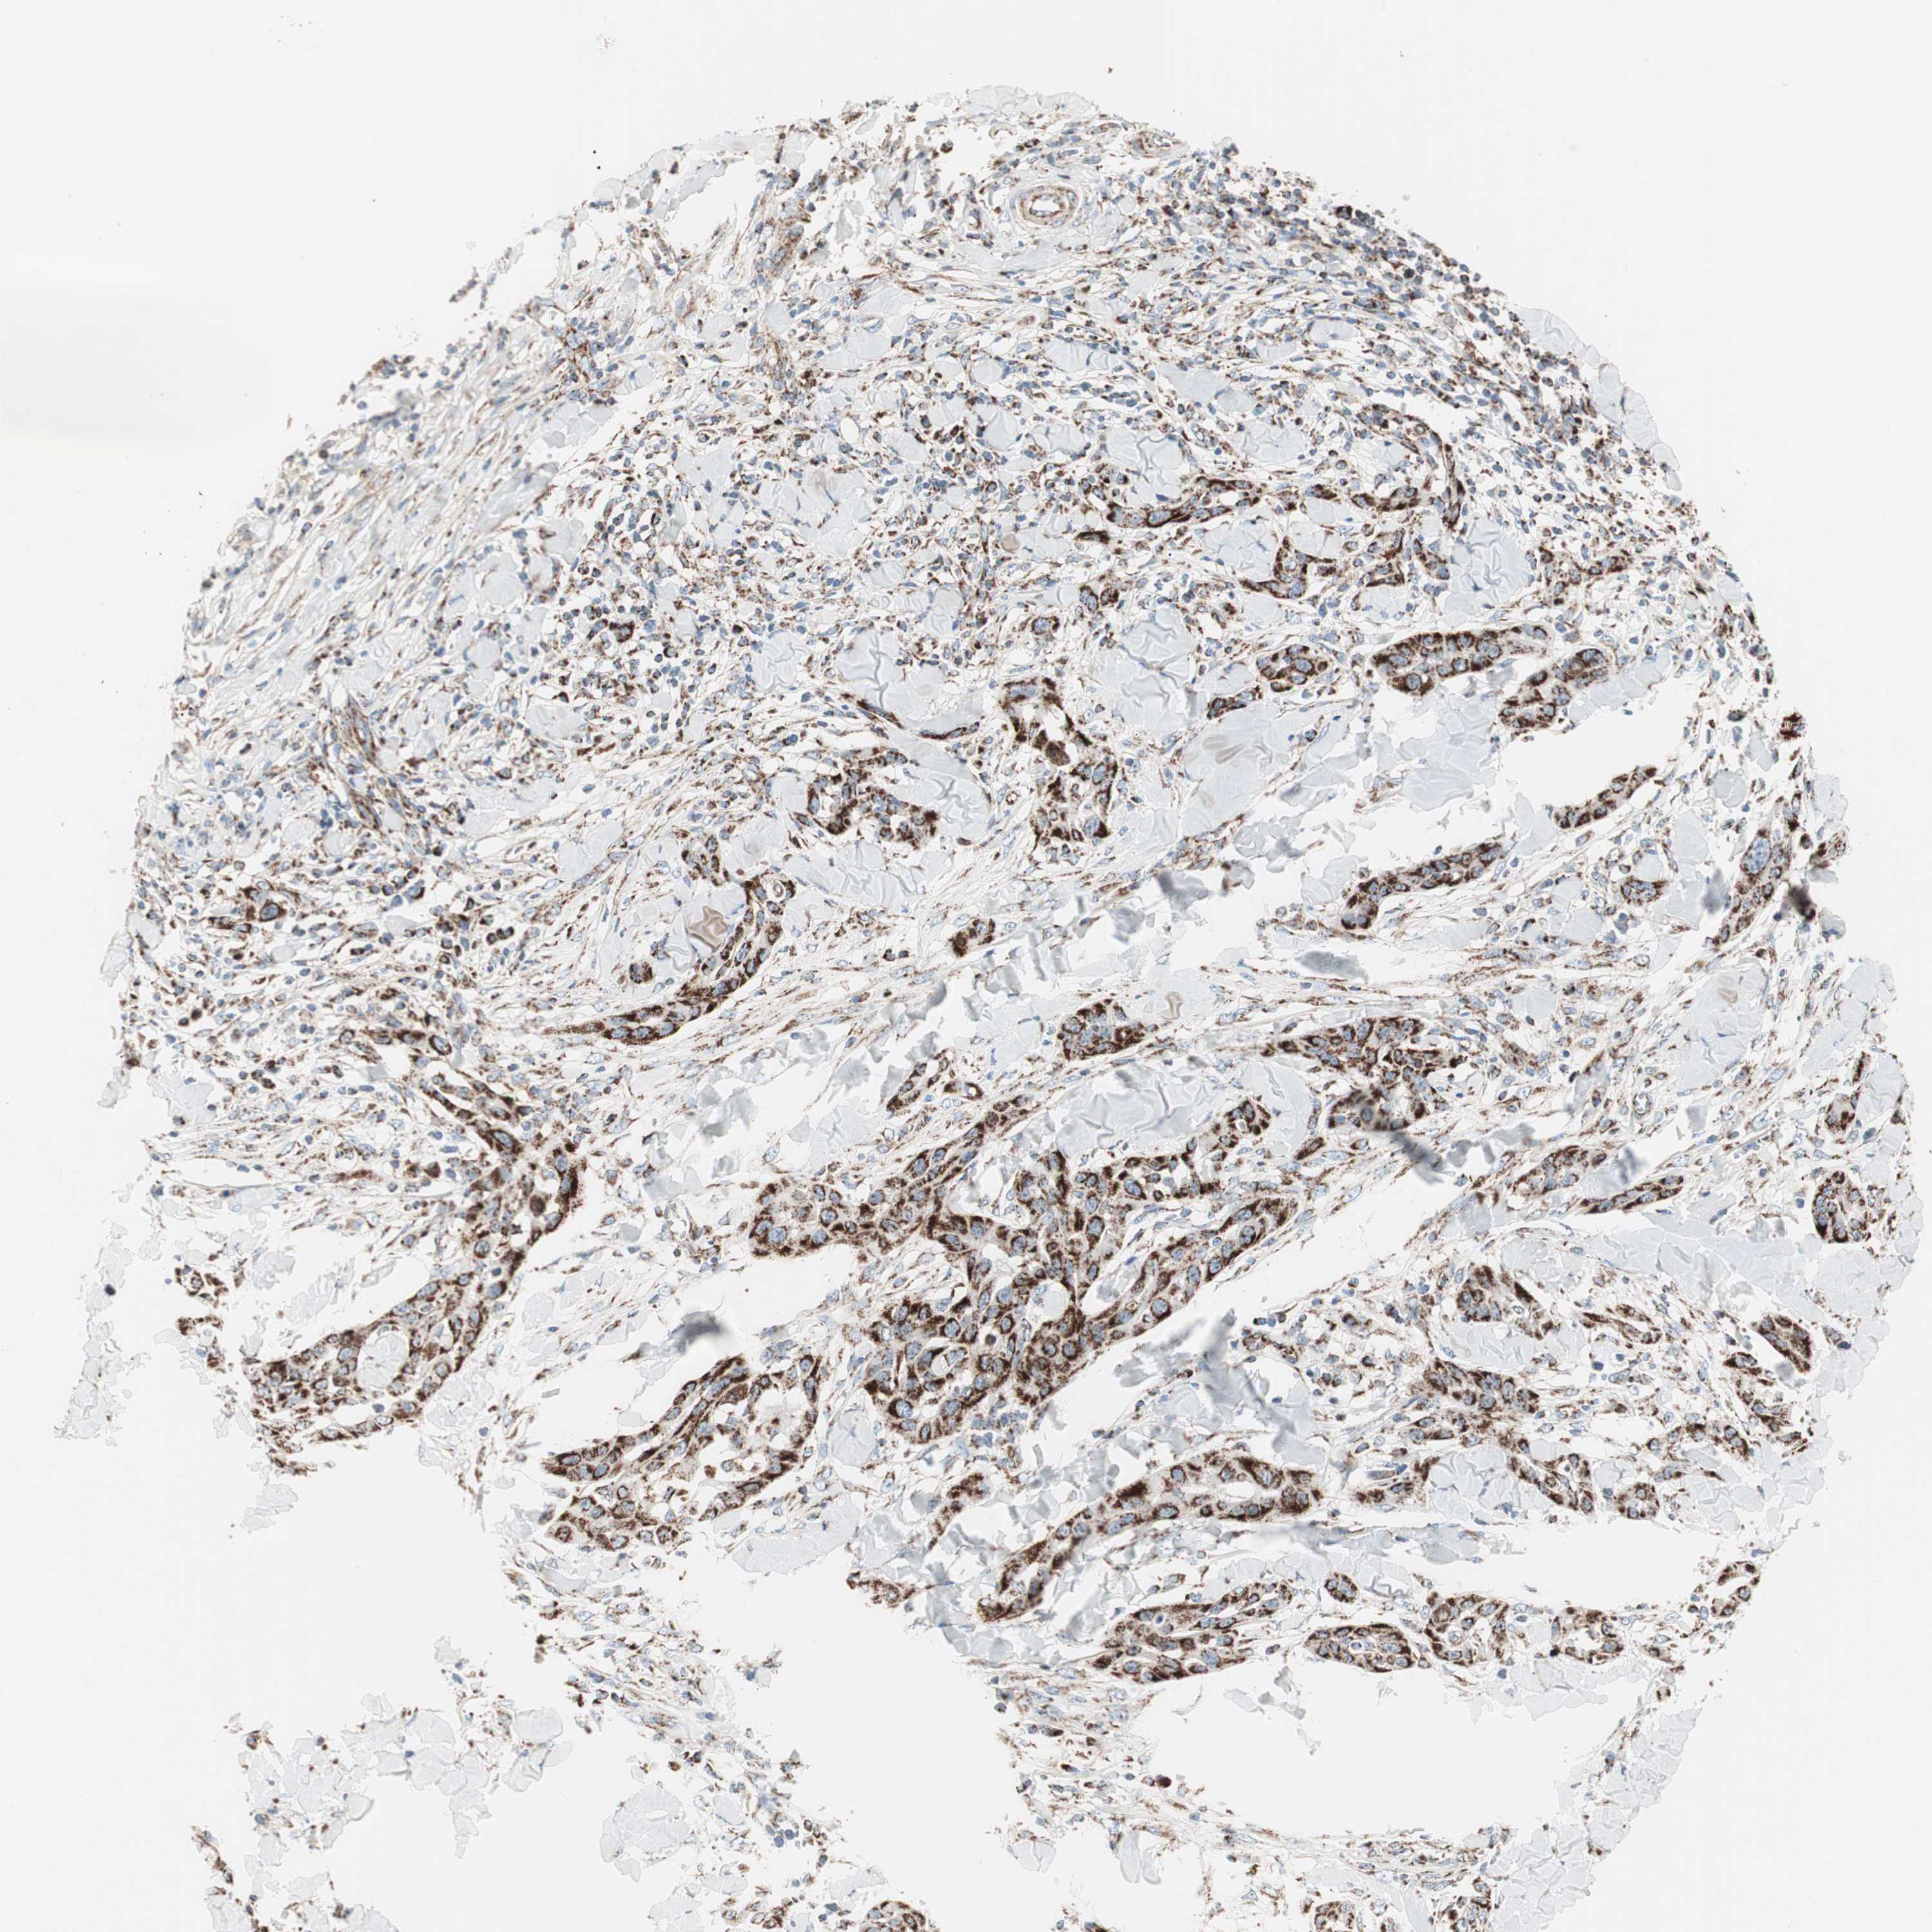

SKIN CANCER - Protein expressioni

A mouse-over function shows sample information and annotation data. Click on an image to view it in a full screen mode. Samples can be filtered based on level of antibody staining by selecting one or several of the following categories: high, medium, low and not detected. The assay and annotation is described here.

Antibody stainingi

Antibody staining in the annotated cell types in the current human tissue is reported as not detected, low, medium, or high, based on conventional immunohistochemistry profiling in selected tissues. This score is based on the combination of the staining intensity and fraction of stained cells.

Each image is clickable and will lead to virtual microscopy that enables deeper exploration of all samples and also displays staining intensity scores, fraction scores and subcellular localization as well as patient and tissue information for each sample.

Antibody CAB005585

Basal cell carcinoma

Squamous cell carcinoma, NOS

Squamous cell carcinoma, metastatic, NOS

Papilloma, NOS